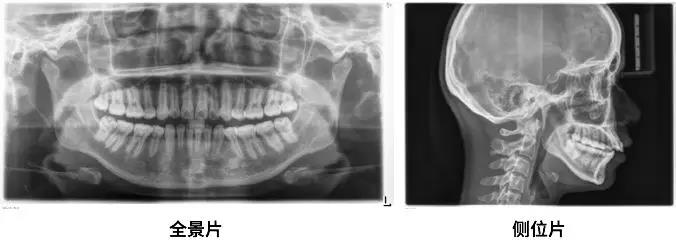

醫(yī)師通常會(huì)讓你拍兩張X光片

一張全景一張側(cè)位

通過(guò)這兩張片子

醫(yī)師能夠?qū)δ愕难例X、牙根、牙槽骨、頜骨

甚至關(guān)節(jié)等進(jìn)行判斷、數(shù)據(jù)分析

看到一些肉眼無(wú)法發(fā)現(xiàn)的問(wèn)題